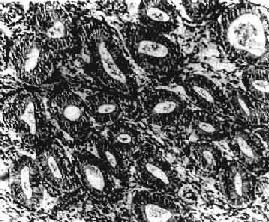

图13-6 子宫内膜增生症

腺体明显增多、大小不一、分布不均,腺上皮多层,间质增生,排列紧密